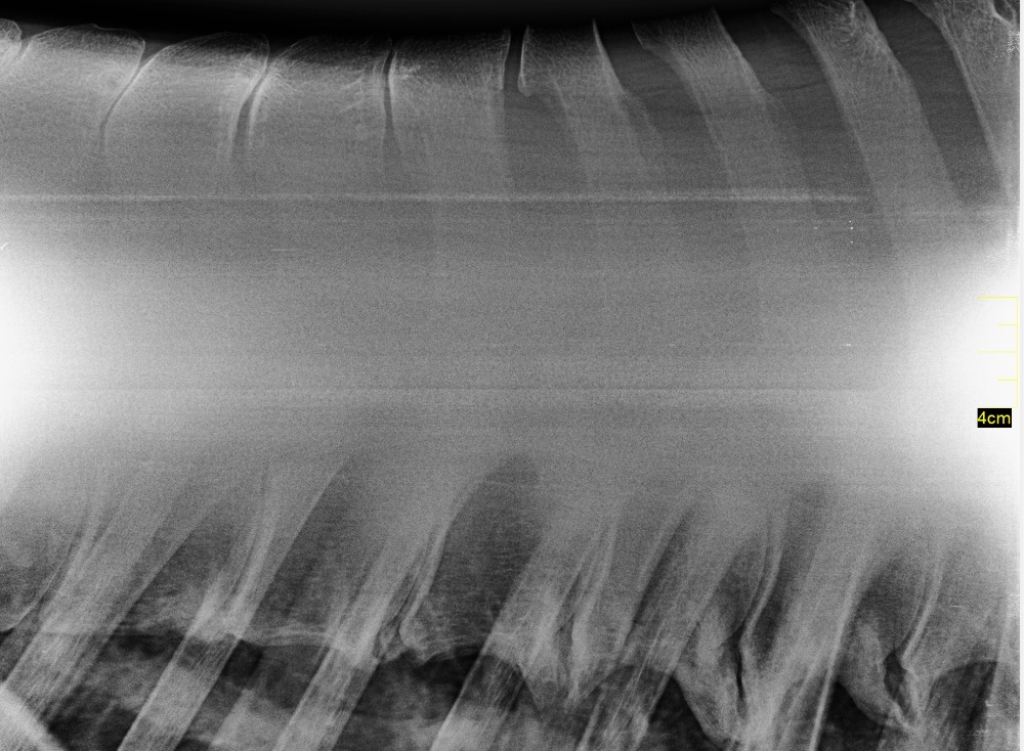

Links: Röntgenopname met daarop botverdichting en botoplossing van de borstwervels

Rechts: Röntgenopname met vormveranderingen van de doornuitsteeksels met daarbij ook botoplossing

Als blijkt dat het om een primair rugprobleem gaat dan is de volgende stap om röntgenopnames van de rug te maken. Op röntgenopnames zijn de doornuitsteeksels en eventuele afwijkingen goed te zien. Verder is het mogelijk om de facetgewrichten van de rug en het SI gewricht echografisch te onderzoeken als daar aanleiding toe is. Om te bevestigen dat de klachten worden veroorzaakt door de kissing spines kunnen we de regio rond de afwijkende doornuitsteeksels tijdelijk verdoven. Als het paard daarna minder klachten vertoont dan is dat een sterke aanwijzing dat de kissing spines de oorzaak (of onderdeel van de oorzaak) is van de klachten.